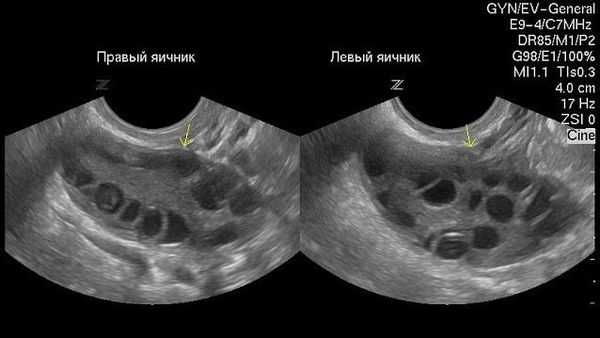

Как выглядят при ультразвуковом обследовании нормальные яичники:

Как выглядят яичники при наличии кист:

При УЗИ-сканировании определяется шаровидное однокамерное образование от 3 до 8 см диаметром, заполненное однородным анэхогенным содержимым. Внутренние стенки кисты ровные, гладкие, имеют толщину 1—2 мм. На фоне фолликулярной кисты визуализируются участки интактной ткани яичника. При допплерометрии выявляются участки кровотока с невысокой скоростью, расположенные по периферии. Фолликулярную кисту дифференцируют от кистомы яичника. В неясных ситуациях прибегают к проведению диагностической лапароскопии.

Безусловно, проведение ультразвуковой диагностики трансабдоминальным и трансвагинальным датчиками позволит не только выявить локализацию кисты, но и определить ее структуру, размеры, характер жидкостного содержимого, определить тактику лечения пациентки. Особенностью фолликулярных кист при ультразвуковом исследовании является тонкостенная капсула с отсутствием сосочков внутренней стороны капсулы. [10] Диагностировать кистозные образования у беременных женщин значительно труднее, ввиду увеличения размеров матки на соответствующих сроках беременности, поэтому ультразвуковое исследование стоит проводить с ЦДК и доплерометрией [11] .